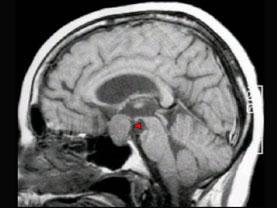

问题 男,37岁,视力模糊,部分视野缺失,伴有头痛、恶心数月,MRI检查如图,最可能的诊断为()

选项 A.颅咽管瘤 B.脑膜瘤 C.蛛网膜囊肿 D.垂体瘤 E.表皮样囊肿

答案 D